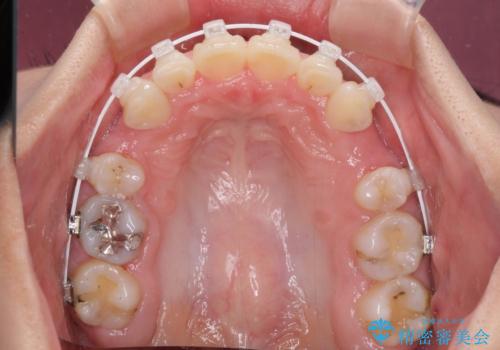

- 審美装置

- 治療期間

- 2年2ヶ月

咬み合わせが深く、咬合力強いため、補助装置を使用しながら積極的に口元を下げることとしました。